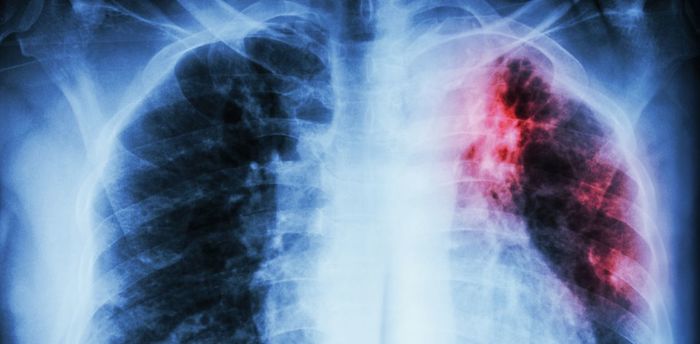

- Рентген грудной клетки и флюорография необходимы при подозрении на туберкулез. Цена – от 300 руб.

В некоторых случаях помимо общеклинических тестов (анализа мочи и крови) могут понадобиться особые инструментальные исследования. К ним относят ультразвуковое исследование брюшной полости и почек, рентгенографию легких и органов грудной клетки. В затруднительных случаях может также потребоваться проведение компьютерной или магнитно-резонансной томографии.